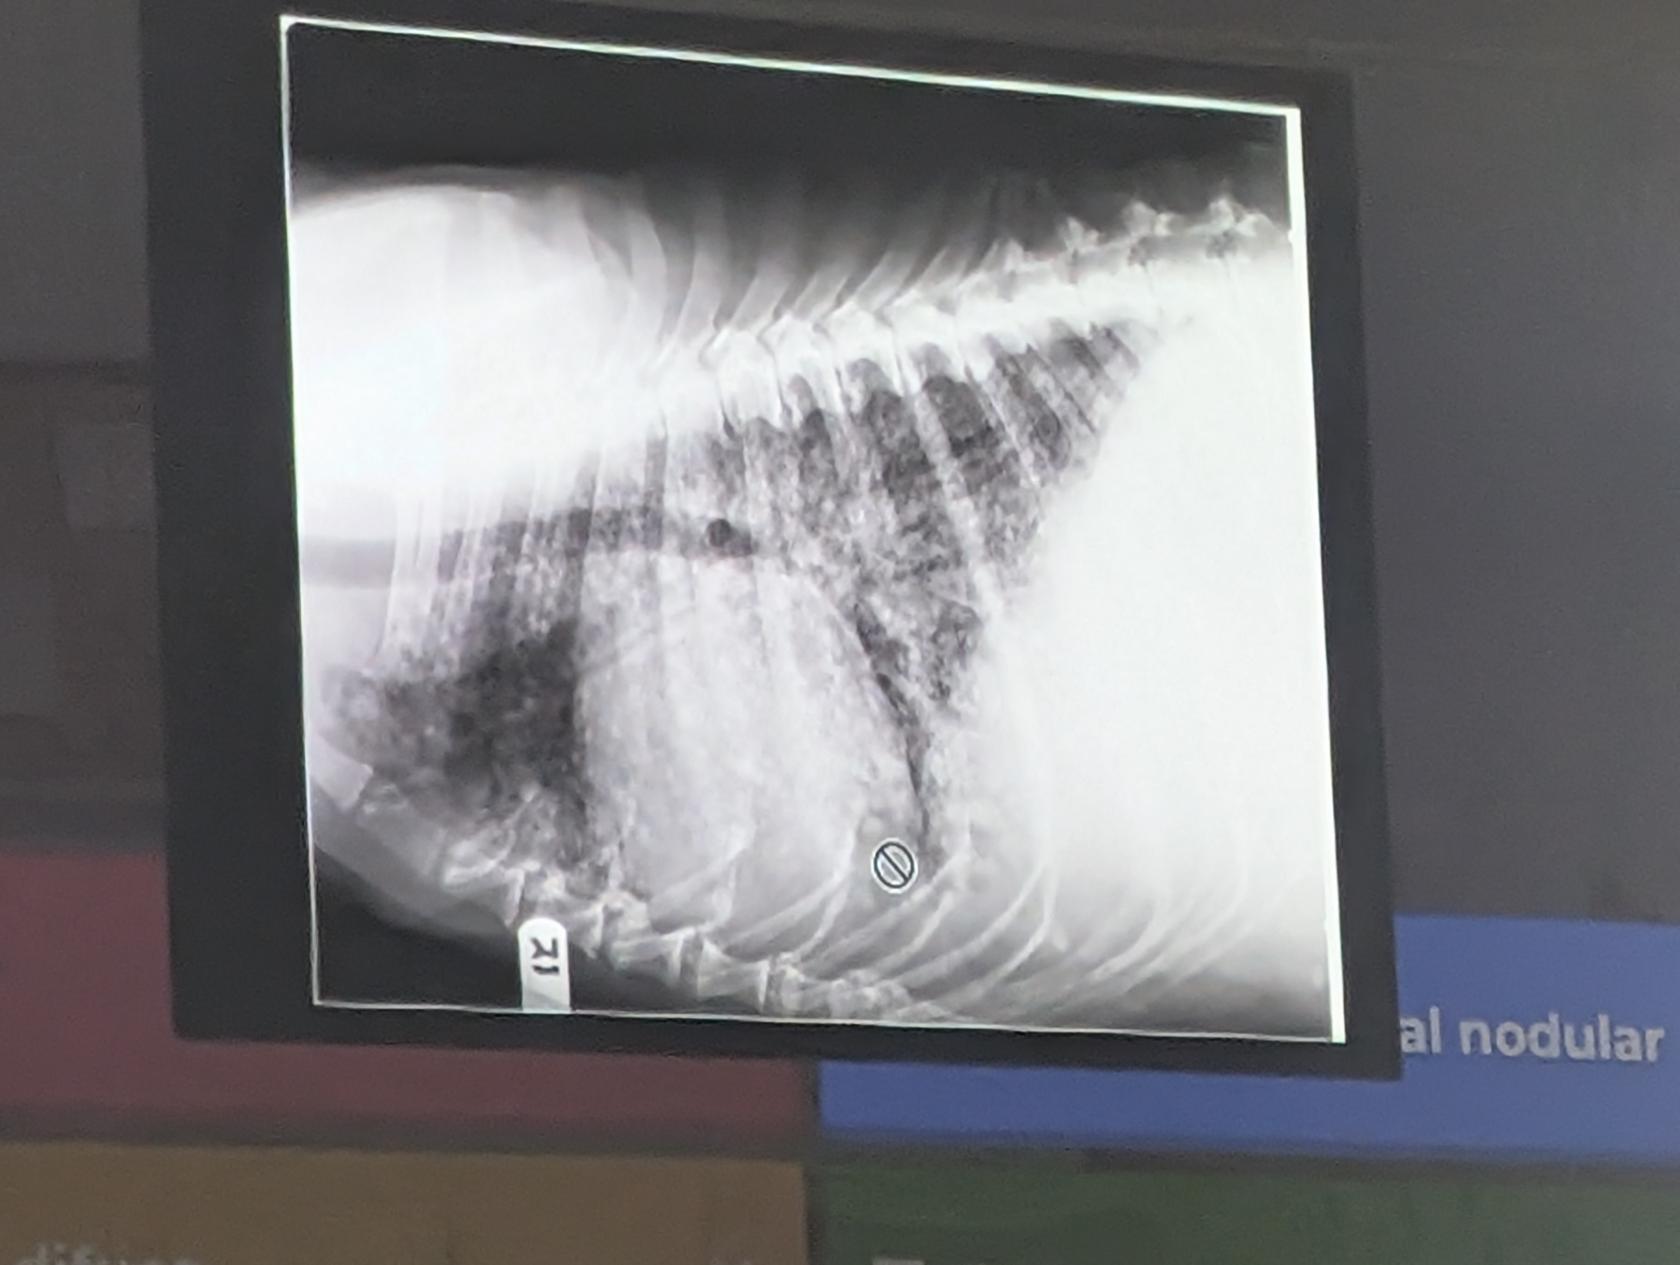

6) Una respuesta correcta

- Patrón intersticial nodular (Además de megacardiomegalia)